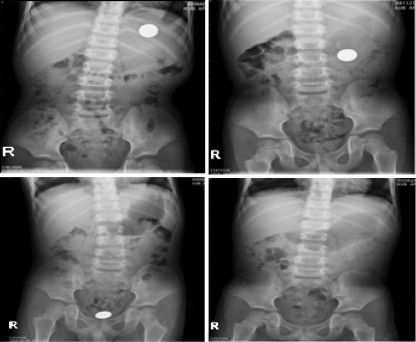

Sebuah foto x-ray menunjukkan koin dalam tubuh manusia Foto: International Journal of Emergency Medicine |

International Journal of Emergency Medicine mencatat kasus yang terjadi pada seorang balita berusia 4 tahun di Taiwan. Balita tersebut tidak sengaja menelan koin besar.

Dikarenakan operasi sangat berisiko, dokter akhirnya meresepkan obat pencahar. 28 hari kemudian, balita tersebut berhasil mengeluarkan koin tersebut tanpa insiden.